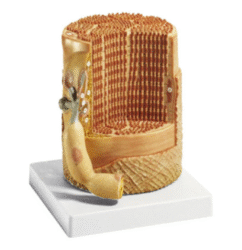

ATL-103 MULTI-FUNCTIONAL INTRA-MUSCULAR INJECTION TRAINING PAD SOFT

The model consists of skin, subcutaneous tissue and muscle layer. Can be used for intradermic injection,hypodermic injection and intramuscular injection. A wearable design makes it convenient for training.Injection liquid can be injected into it, squeeze the pad after use.

Packing: 32pcs/carton, 62x29x29cm, 16kgs